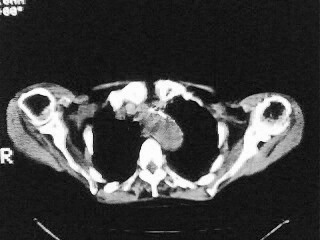

女,79,咳 嗽月余,无其它不适

1)两肺炎症。2)食管裂孔疝可能;建议行上消化道钡餐检查。

(1)食管裂孔疝(2)贲门失弛缓症。建议行上消化道钡餐检查。

后纵隔内左心房至肝左叶后方椎体中线偏左巨大软组织包块,其壁均匀比较薄,其内可见宽气液平。

考虑食管裂孔疝。建议钡餐检查